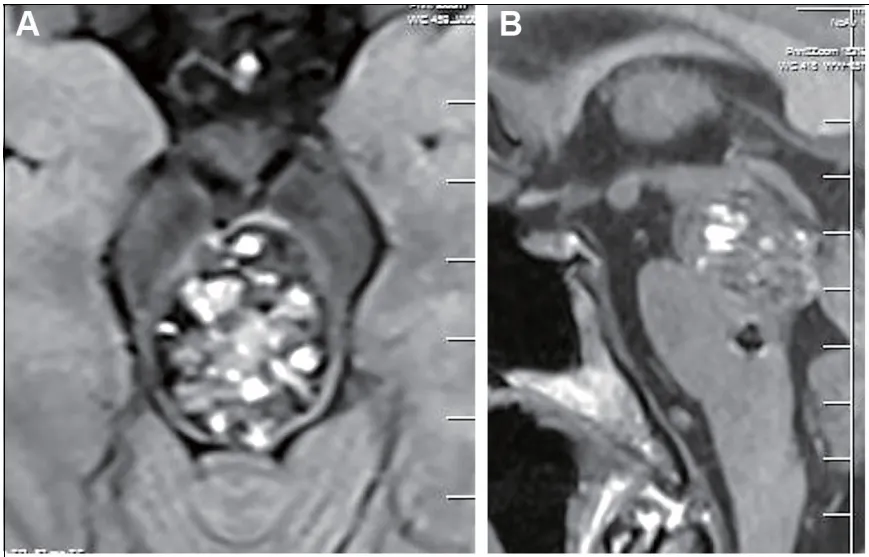

术前增强磁共振成像清晰地显示了病变:轴位和矢状位图像上,一个明显的血管畸形团块。仔细看,还有一个容易被忽略的细节:一个微小“卫星病灶”,静静地躺在脑桥位置。

术前:轴位和矢状位增强磁共振成像